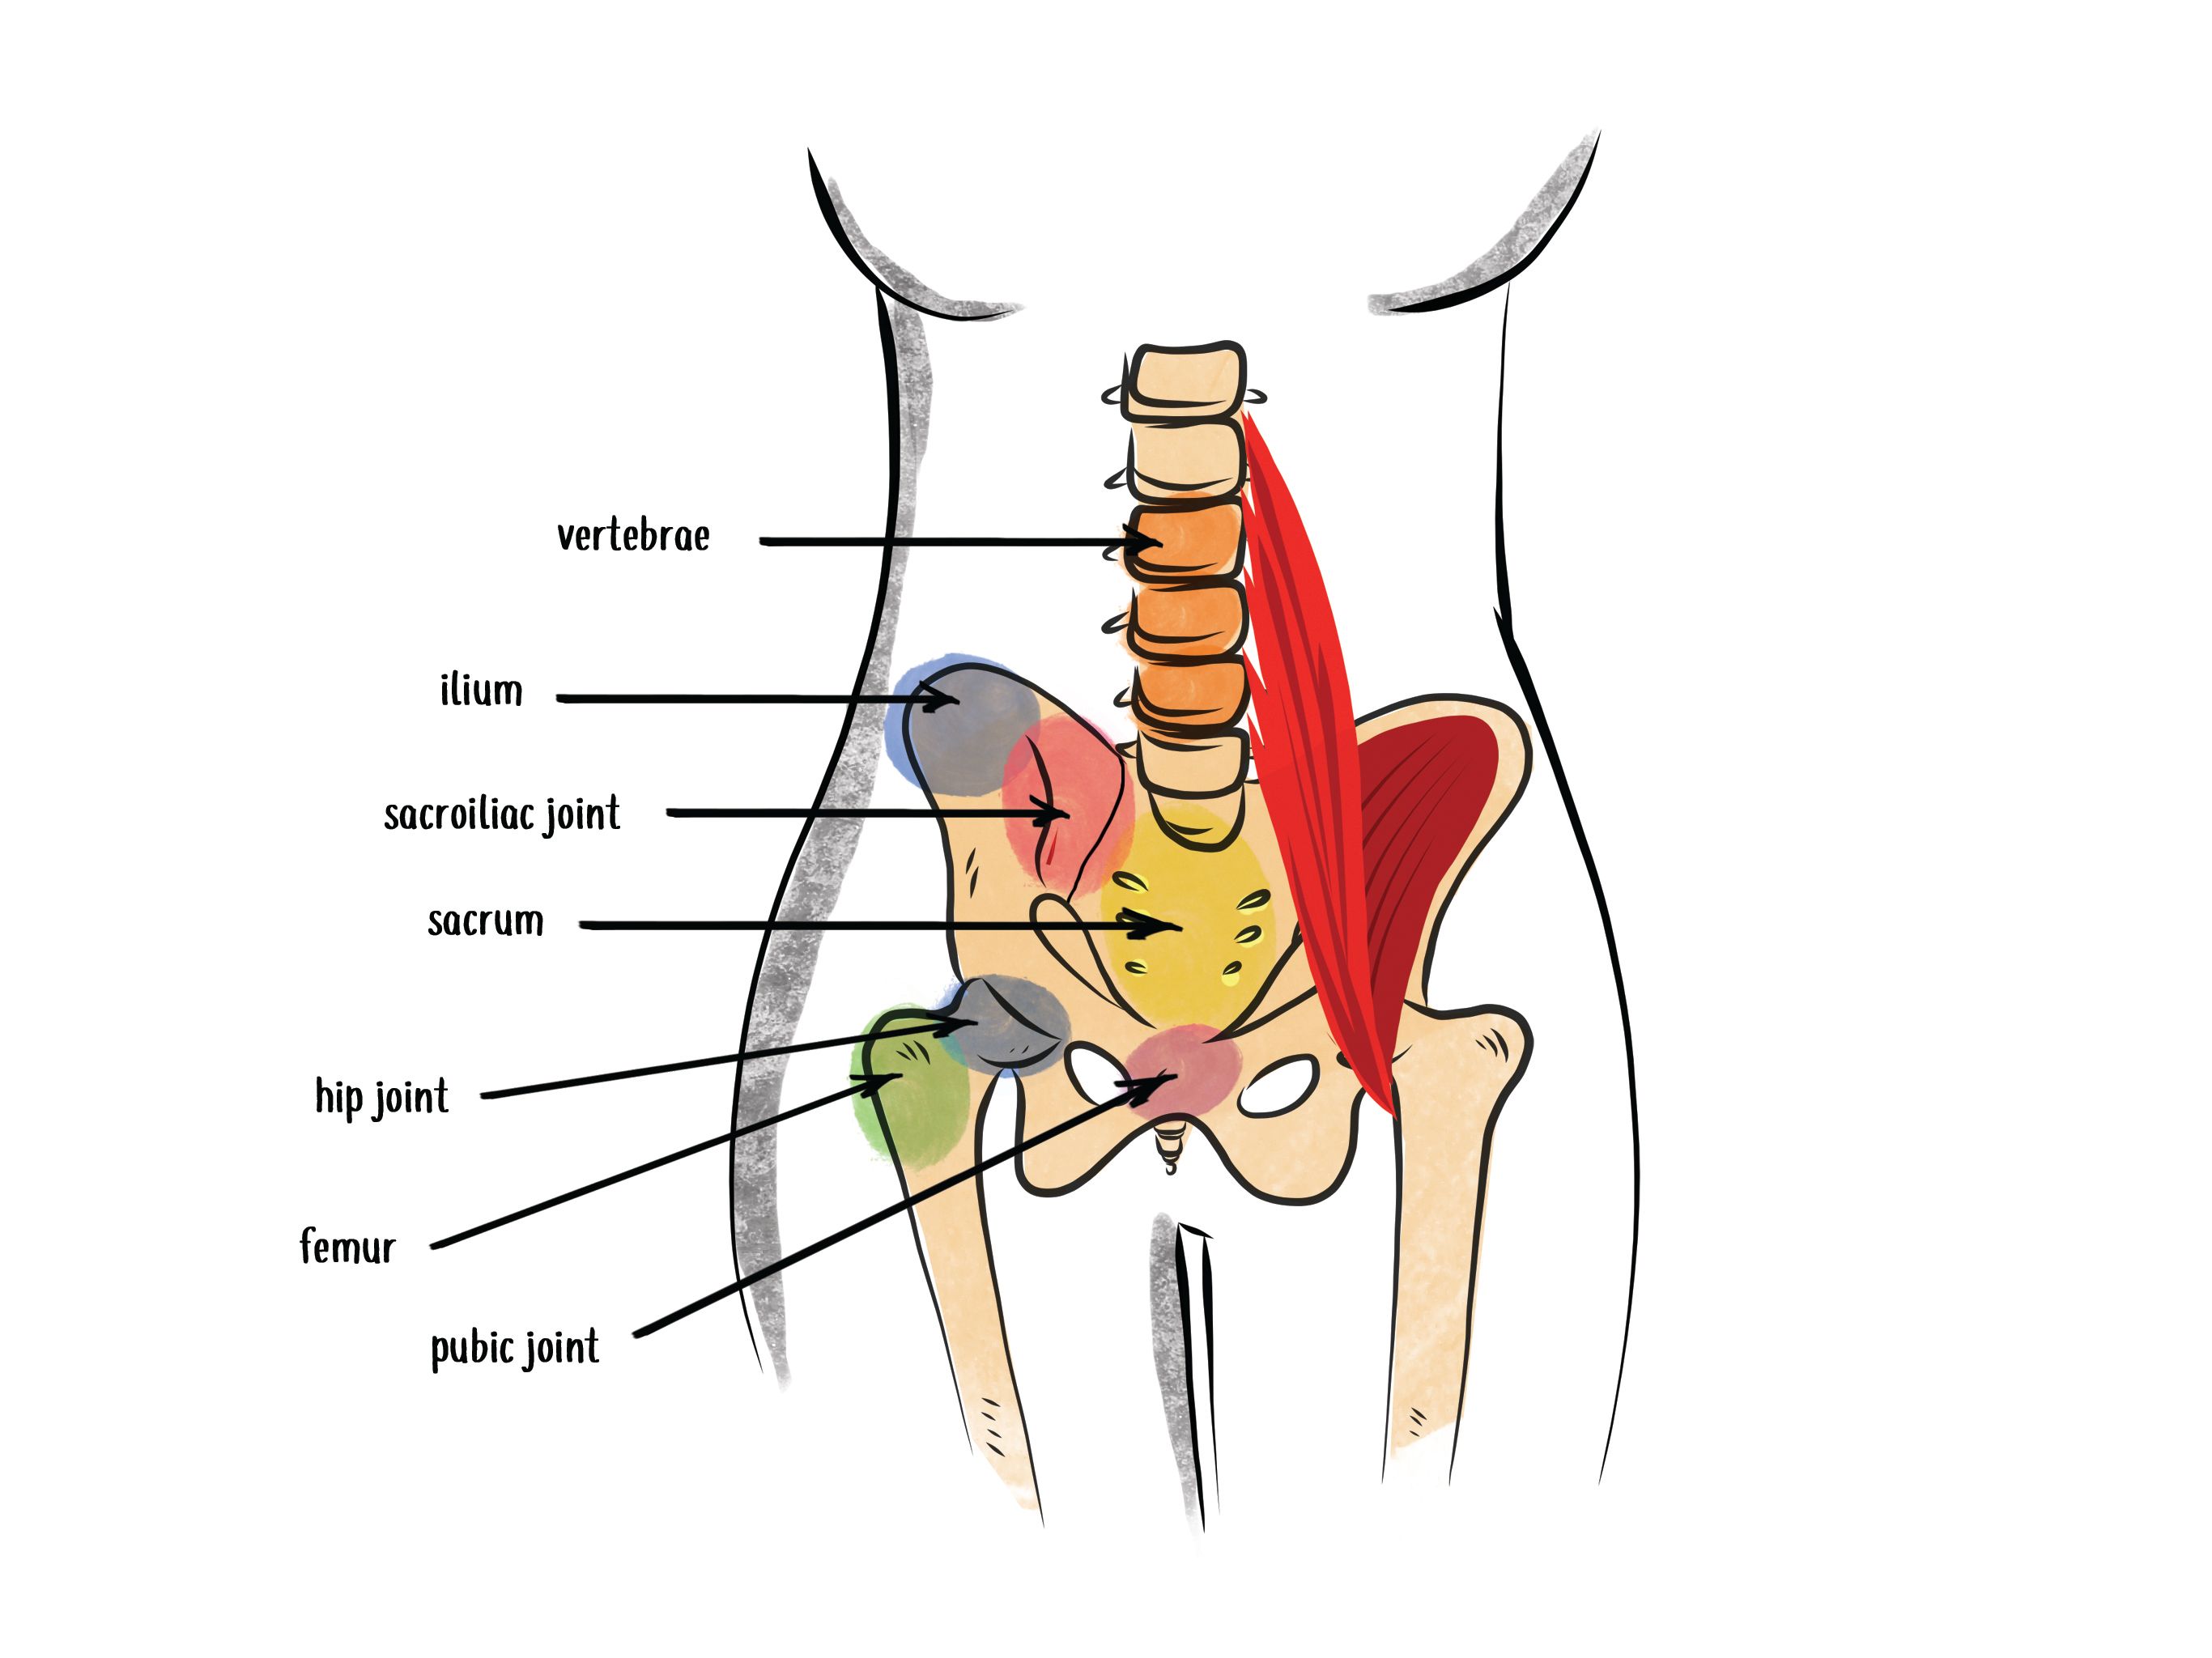

It’s important to understand your anatomy to pinpoint the culprit of your pain when sitting, so let’s make sure you know what your tailbone is!

The tailbone is the same thing as your coccyx and is made up of 3-5 fused vertebrae. Several muscles, tendons, and ligaments connect to your tailbone, and the location at the base of your spinal column makes it a common area to experience pain from trauma or other causes.

Your hip flexors are also known as the iliopsoas muscles. This is the connection of your iliacus and psoas muscles that allow hip flexion actions such as squatting, standing from sitting, stepping up, running, walking, etc.

Your psoas muscle attaches to your spine, and the iliacus muscle attaches to your pelvis. Together they are responsible for the alignment of your lower back and the SI joint.